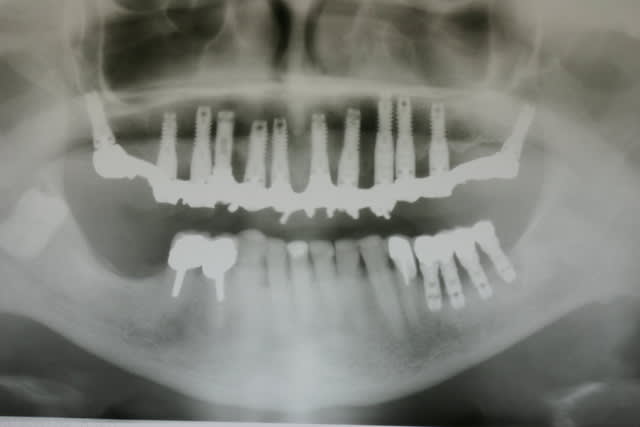

Voici le dentascan de la mandibule que je viens d ostéotenser ce jour. Deuxième séance ds 45 j et puis 45 plus tard implants en enfouis probablement

Zones molaires creuses et zones des PM denses car deux tori mandibulaires sont présent

Dès que les implants y seront vous le saurez mais vu la forme assez bizarre de la mandibule en zone molaire il y aura d abord un modèle Materialise avant la chirurgie, histoire de voir si les plaques sont indispensables ou si les disks pourront passer ds ce relief assez "courbe"